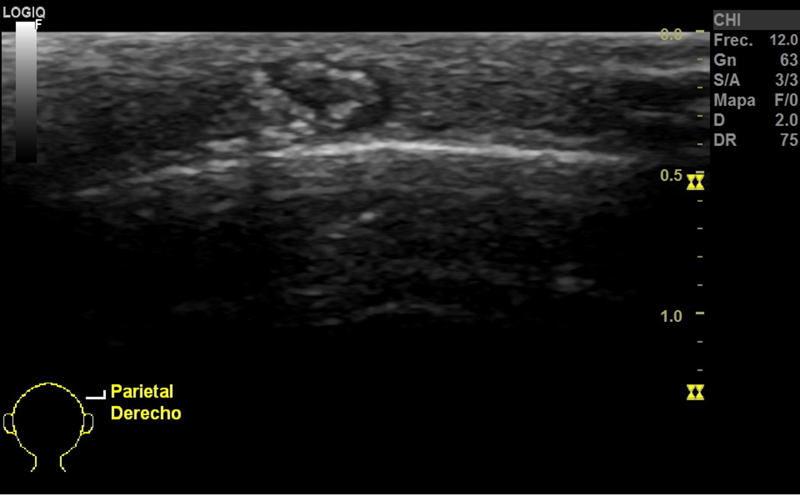

Niña de 8 años, sin antecedentes de interés, que consulta en Atención Primaria por un nódulo en el cuero cabelludo que han detectado recientemente. No asocia dolor ni fiebre ni clínica constitucional. A la exploración presenta un nódulo de consistencia dura de 1 x 1 cm de tamaño en la zona parietal derecha, sin cambios de coloración en su superficie ni signos de sobreinfección.